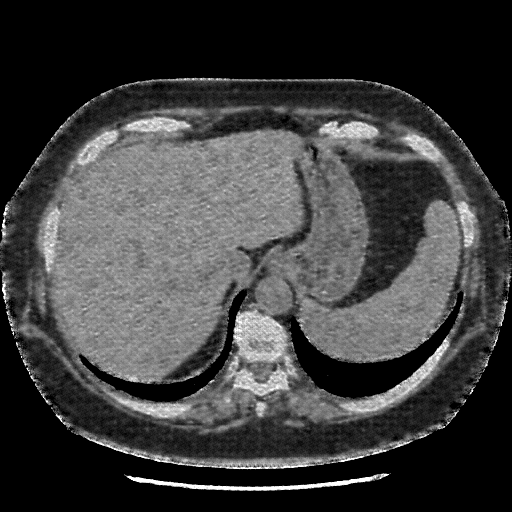

Original NATIVE CT scan (input)

Full window (WL 1023.5, WW 4095 β†’ Low βˆ’1024, High +3071)